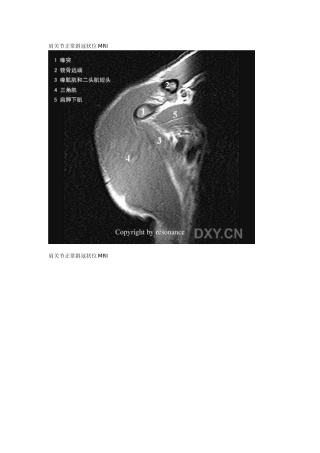

肩关节正常斜冠状位 MRI肩关节正常斜冠状位 MRI肩关节正常斜冠状位 MRI肩关节正常斜冠状位 MRI肩关节正常斜冠状位 MRI肩关节正常斜冠...